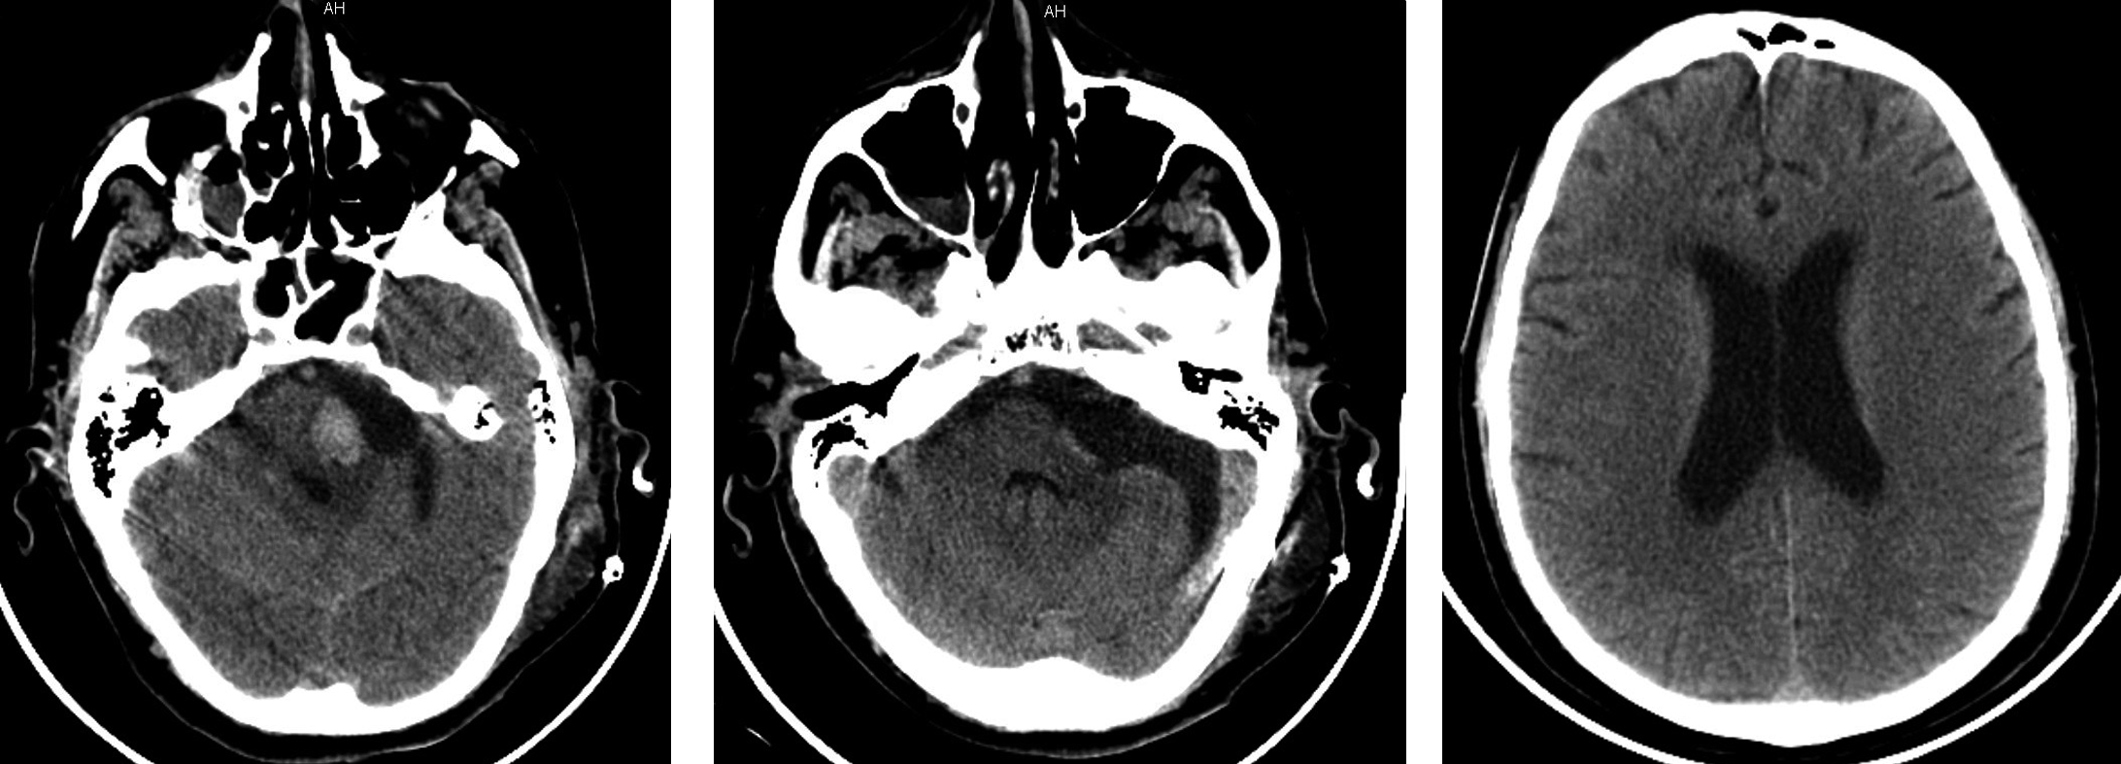

After waking up from sedation, the patient regained clear consciousness. However, it was not possible to wean him from the mechanical ventilation due to rapid exhaustion and blood gas disturbance during independent breathing, so respiratory support in SIMV mode was provided. Systolic BP was fairly stable ranged from 140 to 160 mm Hg with an increase during independent breathing. Facial palsy progressed up to House–Brackmann grade V–VI [14], left-side facial numbness and fine horizontal left-beating nystagmus developed. There were no motor symptoms or any damage to other cranial nerves. Control MSCT (Fig. 2) revealed an area of hemorrhage up to 1.5–2.0 ml in the left regions of the pons. There was no hemorrhage in the tumor bed. The ventricular system was moderately dilated, but, compared to preoperative levels, no increase in volume was observed.

Fig. 2. Contrast-enhanced head MSCT on postoperative day 1. No contrast-enhancing areas observed. Hemorrhage site is detected in the left regions of the pons.

Over the next few days, the patient varied from being clearly conscious to mild obtundation. Respiratory support in SIMV mode was continued. Repeated attempts to wean the patient from the MV failed due to the rapid increase in respiratory failure. There were episodes of BP increasing up to 150 mm Hg. No cardiac arrhythmias were observed. Based on MSCT data (Fig. 3), neither progression of hydrocephalus, nor increase of hemorrhage area in the pons region, nor brainstem involvement were detected.

Fig. 3. Head MSCT on postoperative day 5.